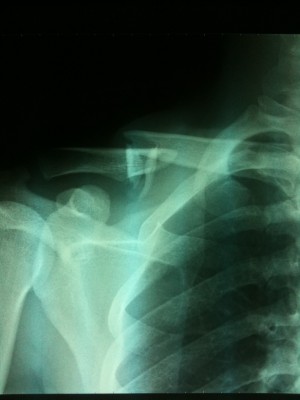

昨年、10月に怪我した鎖骨もだいぶ良くなってきて、